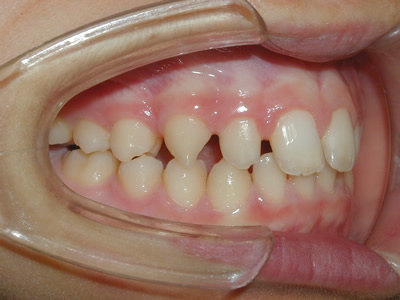

永久歯に交換するためのスペース不足による前歯のガタガタで、取り外しができる拡大床にて上下顎の幅を拡大した後、上顎の前歯をマルチブラケット装置で並べました。治療の期間は1年9か月でした。

終了時